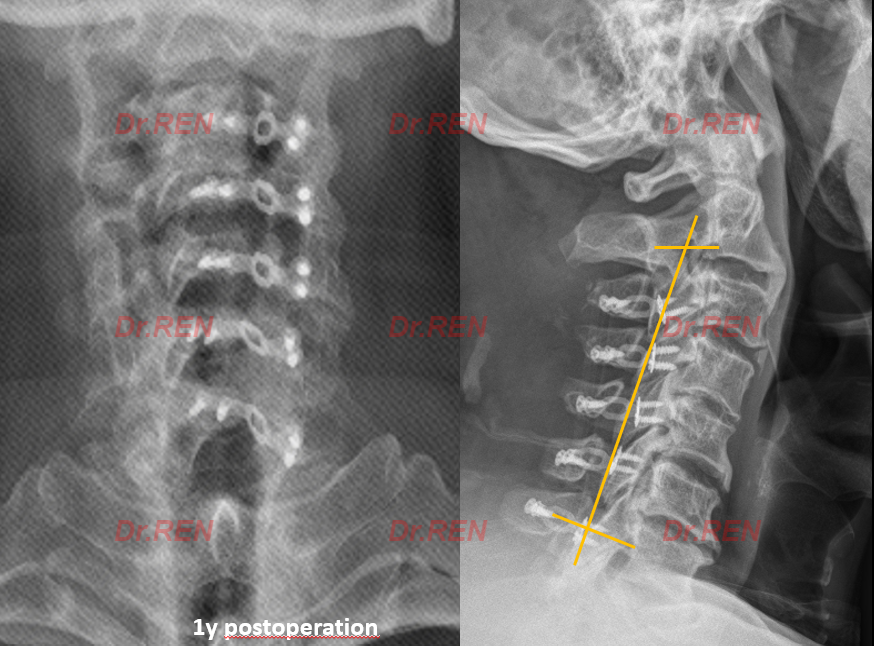

患者采取了后路椎板成形术(单开门)行彻底减压,同时保留了患者的运动节段。我们看一下术后的影像检查:

术后核磁显示患者颈椎管容积明显扩大,脊髓压迫解除。

患者术后2天下地活动,术后6天出院;一年后随访颈椎曲度保持良好。患者恢复良好。